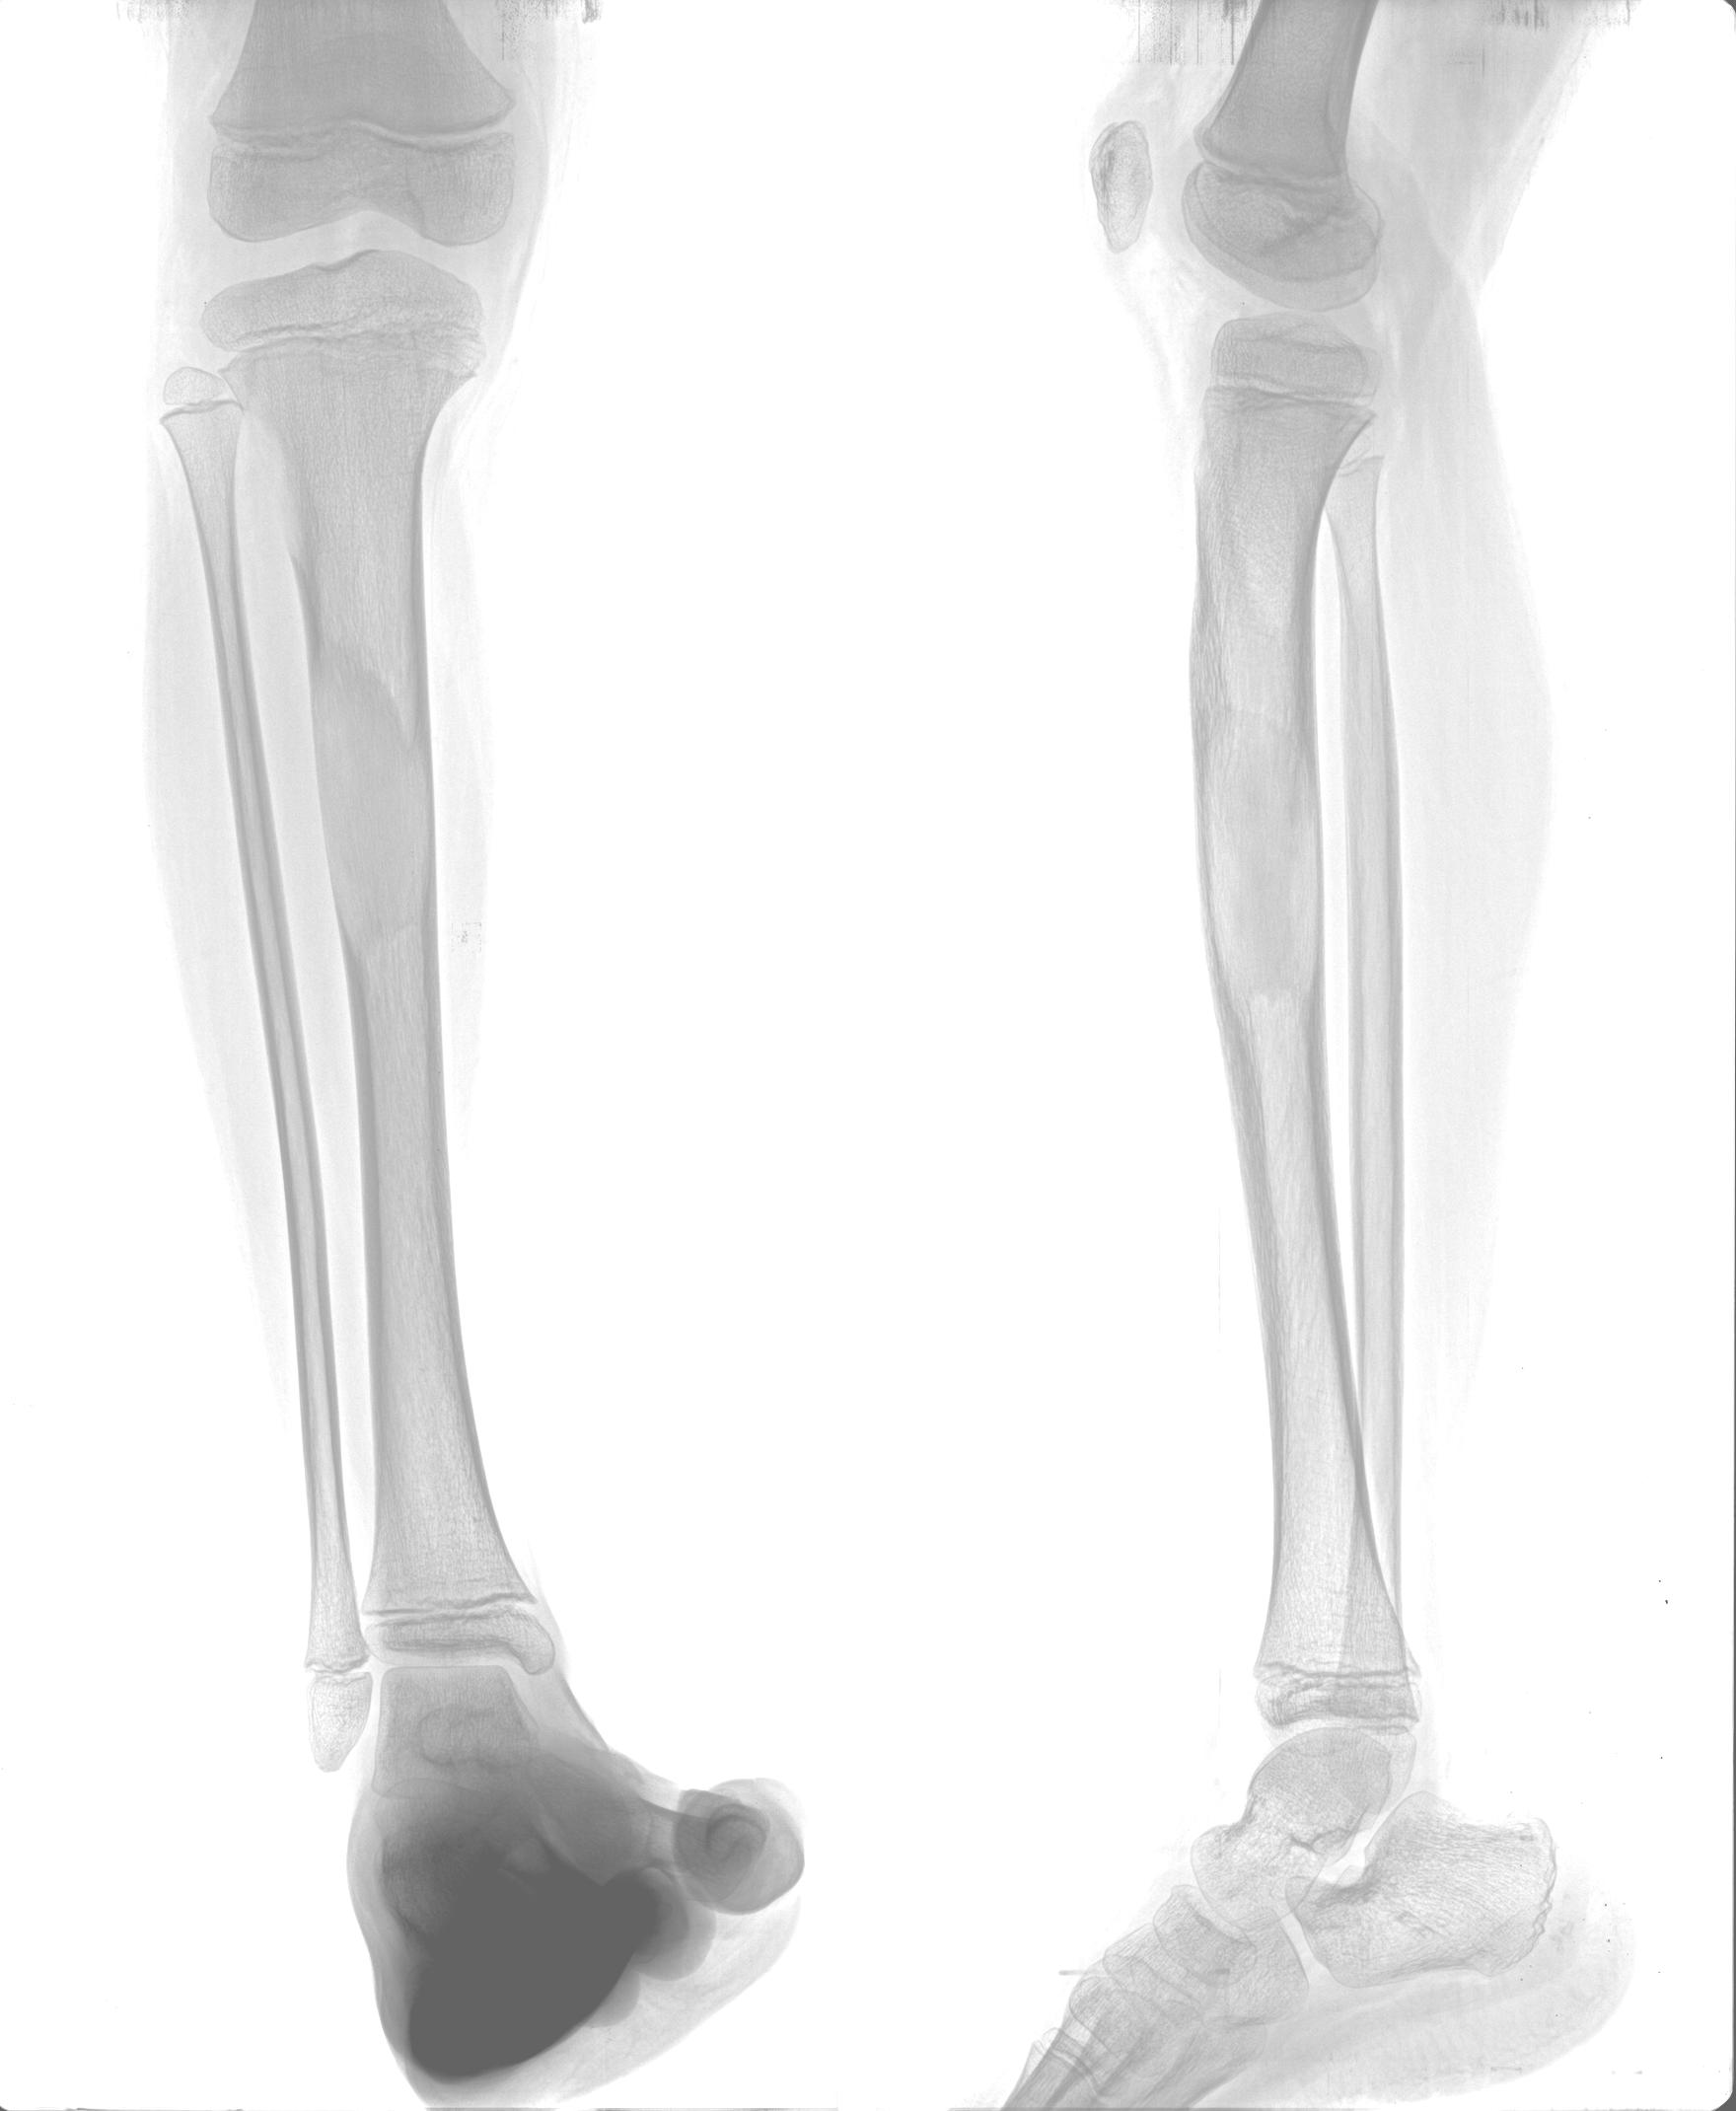

以下是引用zhangzhongshou在2008-5-24 13:32:00的发言:[br]胫骨膨胀性骨质破坏区,骨皮质变薄,内呈磨玻璃状模糊影,符合胫骨骨纤维异常增殖症。

以下是引用dyqct在2008-5-24 16:56:00的发言:[br]磨玻璃状模糊影,符合右胫骨骨纤维异常增殖症。 [br] [br]